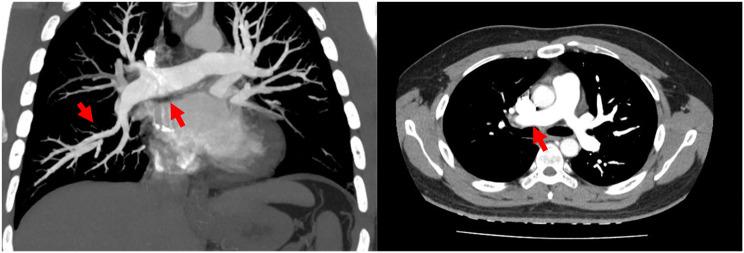

Pulmonary embolism is the most common cardiovascular disease after myocardial infarction and stroke. Konstantinides (Eur Heart J 41(4):543-603, 2020) Current guidelines categorize patients with PE as being at low, intermediate, and high risk of early death, with the intermediate-risk group experiencing the greatest uncertainty regarding treatment recommendations. Rapid reduction of the thrombus load by thrombolysis significantly reduces symptoms and decreases mortality, but is accompanied by a high risk of bleeding. Meyer (N Engl J Med 370(15):1402-11, 2014) Mechanical thrombectomy (CDTE) have been proven safe and efficient, yet current ESC guidelines suggest the utilization of catheter interventions only for hypotensive patients with high bleeding risk, failed systemic thrombolysis, and cardiogenic shock or if a patient does not respond to conservative therapy Konstantinides (Eur Heart J 41(4):543-603, 2020). Here, we report a case of an intermediate-risk patient with pulmonary embolism who underwent thrombus aspiration and showed significant improvement in symptoms after treatment.